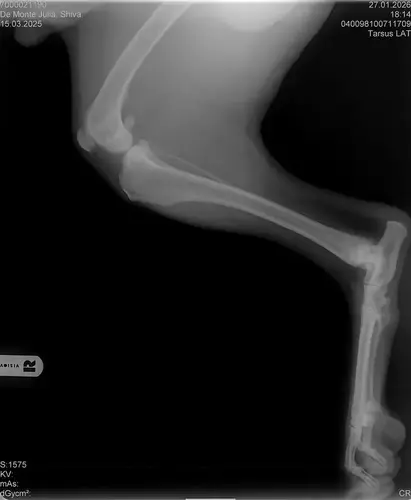

Vorige Woche kam mir Shiva verändert vor, nicht der aufgeweckte Spaßvogel der er sonst ist. Ich dacht vl ist er im Garten iwie blöd ausgerutscht weil unser gesamtes Grundstück über Wochen von einer dicken Eisschicht überzogen war. Er lag viel rum, zuviel da er doch zu den Wirbelwinden unter den Junghunden gehört. Er quetschte sich zum schlafen an mich ran, was auch untypisch für ihn ist. Er ist immer so „iiiii fass mich nicht an“. Ich nehms ihn nicht böse er ist nicht der große Kuschler :D Hat er wohl von mir :D :D aber er pickte nur an mir dran, ruhen ohne Körperkontakt war nicht möglich. Fand ich schön aber da ich wusste dass es nicht Shiva ist machte ich mir schon Sorgen… Am nächsten Tag wollte ich ihn bürsten alles war wie immer, er legte sich hin und sah mir zu wie ich einen Fellberg stapelte. Bei seinen Hinterpfoten hörte ich auf und dachte mir ich fühl mal vorsichtig.. Plötzlich knurrte er mich an vor Schreck weil ich damit überhaupt nicht gerechnet hatte zuckte ich reflexartig zurück (was lt Trainerin ein Fehler war)… Aber ich hab nicht mit einer derartigen Reaktion gerechnet, Shiva hatte schon 2 kleine Verletzungen die ich ohne Probleme verarzten konnte. Am nächsten Tag gings ab zum TA. Mit Maulkorb da ich nichts riskieren wollte. Nach der Untersuchung wo er auch mehrmals knurrte gings ab zum röntgen. Und das riss mir den Boden unter den Füßen weg. Dann die Aussage von der TA „ich weiß sie wollen einen gesunden jungen Hund aber das ist Shiva leider nicht“. Was jetzt? Er ist so ein aufgewecktes Kerlchen, absolute Lieblingsbeschäftigung ist Parcour. Er macht es so gern, ja auch UO und Suchspiele aber das leuchten in seinen Augen wenn wir Geräte machen :( (er macht noch keine schweren Geräte wie A Tafeln oder springen… Aber die seichten macht er mit absoluter Leidenschaft.. Ruhe halten über mehrere Monate… nur langsames gehen oder schnüffeln.. puh ich weiß nicht wie ich ihm verbieten soll zu rennen und zu toben… Vl habt ihr Tipps für mich. Im Anhang der Befund und ein paar Bilder vom kleinen Wirbelwind. <3

• Naja die Diagnose kommt von einem „Facharzt“, lt TA war ihrerseits alles i.O. Sie wollte noch sicher gehen und die Bilder zur weiteren Befundung einschicken und das kam dabei raus. Und der Therapievorschlag beläuft sich auf Ruhe, Ruhe und noch mehr Ruhe. Und einer Schmertherapie von Gabapentin 800mg 1/2 Tablette 2x tgl, Carprodyl 120mg 1 1/2 Tabletten 1x tgl und TamaCan CBD Tropfen 10-15 Tropfen 2x tgl. 1x in der Woche soll ich telefonisch Auskunft geben wie es Shiva geht. Das ganze mal für 14 Tage. Sie meinte noch sie hat viele Junghunde die ein Leben lang Schmerzmittel nehmem müssten. Die Röhrenknochenentzündung heilt in der Regel von selber der Rest gehört beobachtet… Ich weiß im Moment auch nocht so recht.. Er tut mir nur wahnsinnig leid mit sovielen Diagnosen und für mich war erstmal vorrangig ihn schmerzfrei zu bekommen. Das ist er inzwischen und versteht die Welt nicht mehr warum er nicht wie sonst spielen und arbeiten darf. Im Anhang noch Röntgenbilder falls sich jemand damit auskennt bzw Interesse hat..

Ich finde es richtig dass erstmal eine Schmerztherapie eingeleitet wird. Die Panosteitis ist wohl schmerzhaft, also evtl. ist das derzeit der einzige Verursacher des Unwohlseins?

Panostitis ist idR sehr schmerzhaft, aber nicht unüblich und heilt in der Regel von alleine aus, wichtig dabei ist schonen und Entzündungshemmer zu geben, damit das nicht chronisch wird. Ich denke, dass die Akut bemerkbaren Schmerzen hauptsächlich davon kommen. Also da passt die Empfehlung deiner TÄ für's Erste auf jeden Fall.